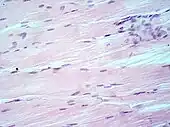

Lung tissue taken from an emphysema patient. Cell nuclei (blue-purple), red blood cells (bright red), other cell bodies and extracellular material (pink), and air spaces (white). Muscle tissue, cell nuclei (blue-purple), cell body (pink).

Muscle tissue, cell nuclei (blue-purple), cell body (pink)..jpg.webp) Basal cell carcinoma of the skin, cell nuclei (blue-purple), extracellular material (pink).